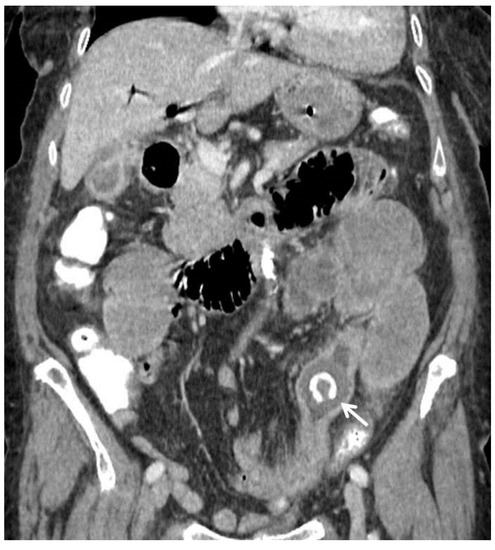

| F, 69 | 12 | III | Colonoscopy | 115 | Sigmoid colon | 5 × 4 cm | - | 10 | Good: recovery |